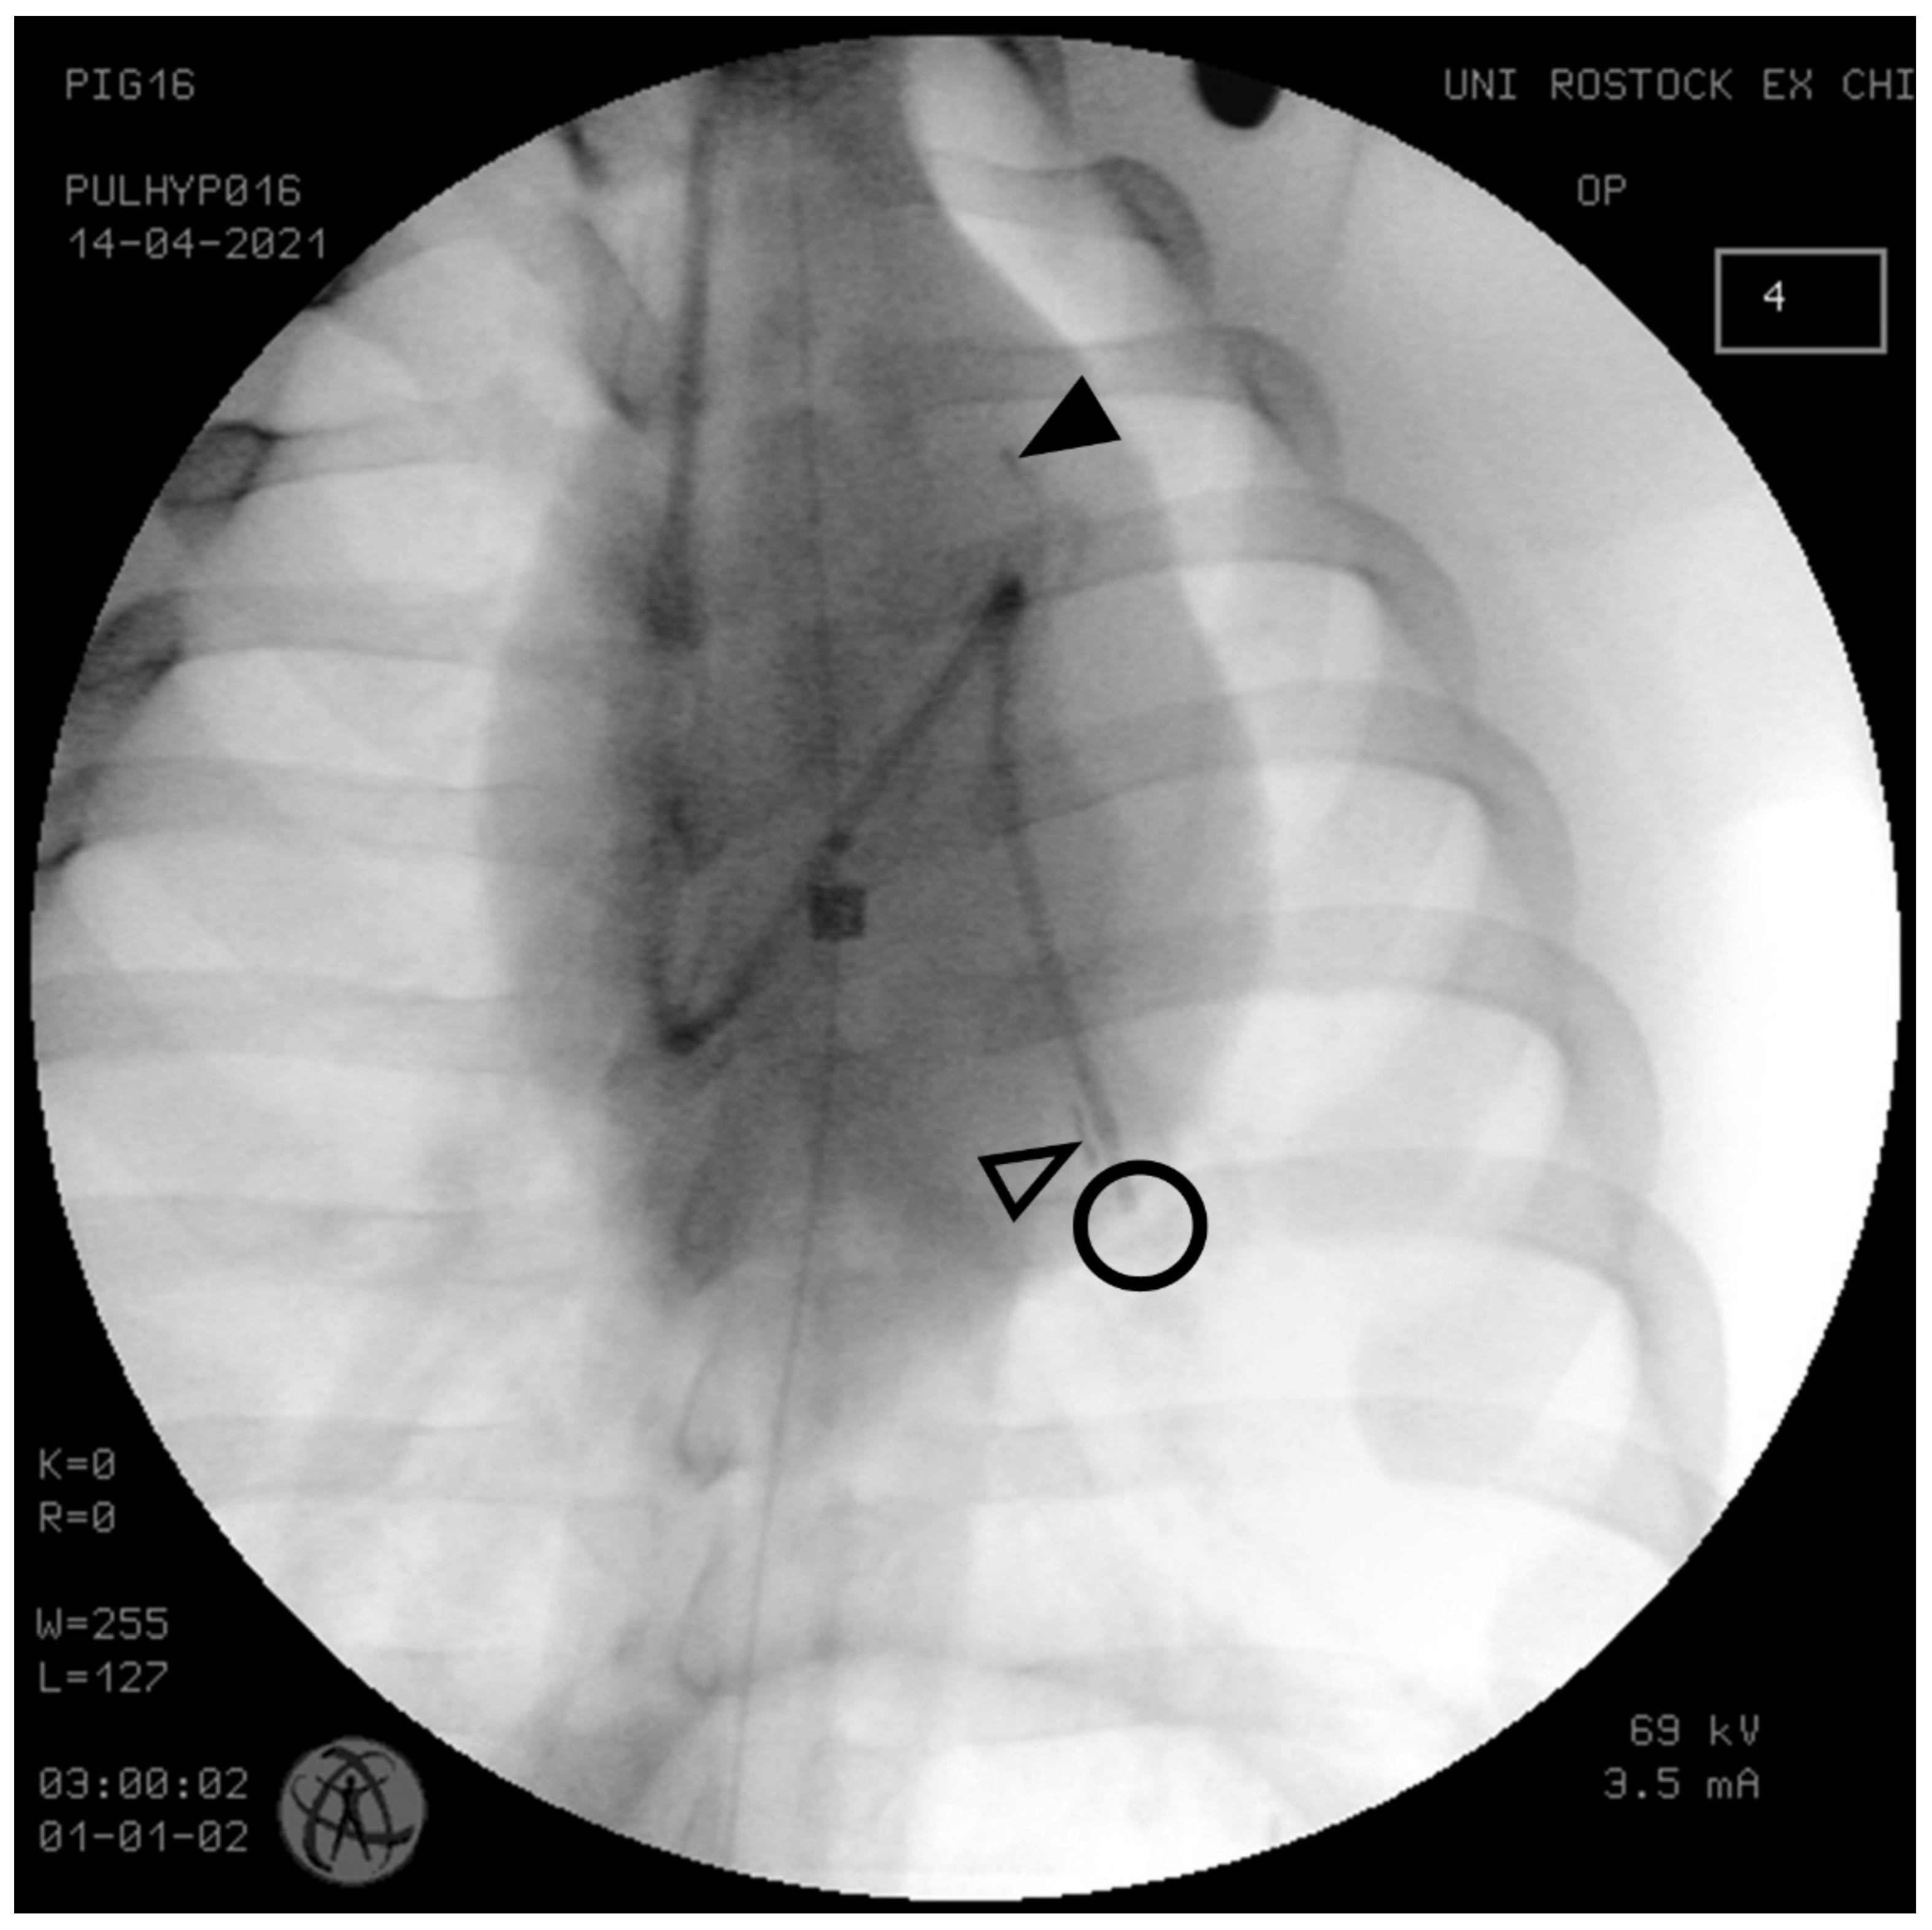

2.2. Instrumentation

2.4. Data Acquisition and Processing